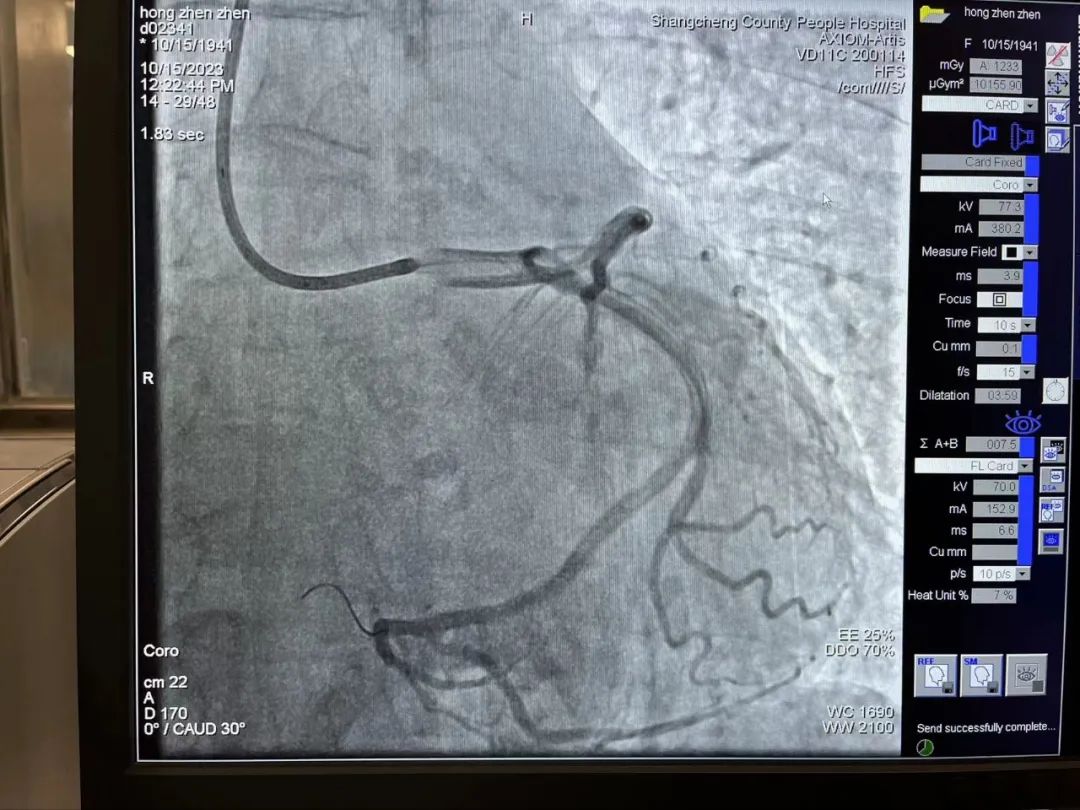

然而,患者急诊冠状造影结果显示:左右冠脉主干血管未见明显狭窄,无法确定“罪犯血管”,但是患者心电图提示下壁仍然持续抬高,胸痛症状得不到缓解,病情扑朔迷离。一直在导管室指导的熊晨晖主任仔细观察了影像结果,发现患者右冠细小,回旋支远端可为右心供血,可能为“功能性右冠脉”,所以考虑回旋支远端为“罪犯血管”。随即邀请郑州大学第一附属医院心内科教授远程会诊,教授同意熊主任的观点,认为左旋支可能是“罪犯血管”,但认为回旋支远端较细、且供血区域局限,介入手术治疗获益不能肯定,可以尝试手术看看效果,也可以先药物治疗。

回旋支未见明显狭窄,远端可见慢血流